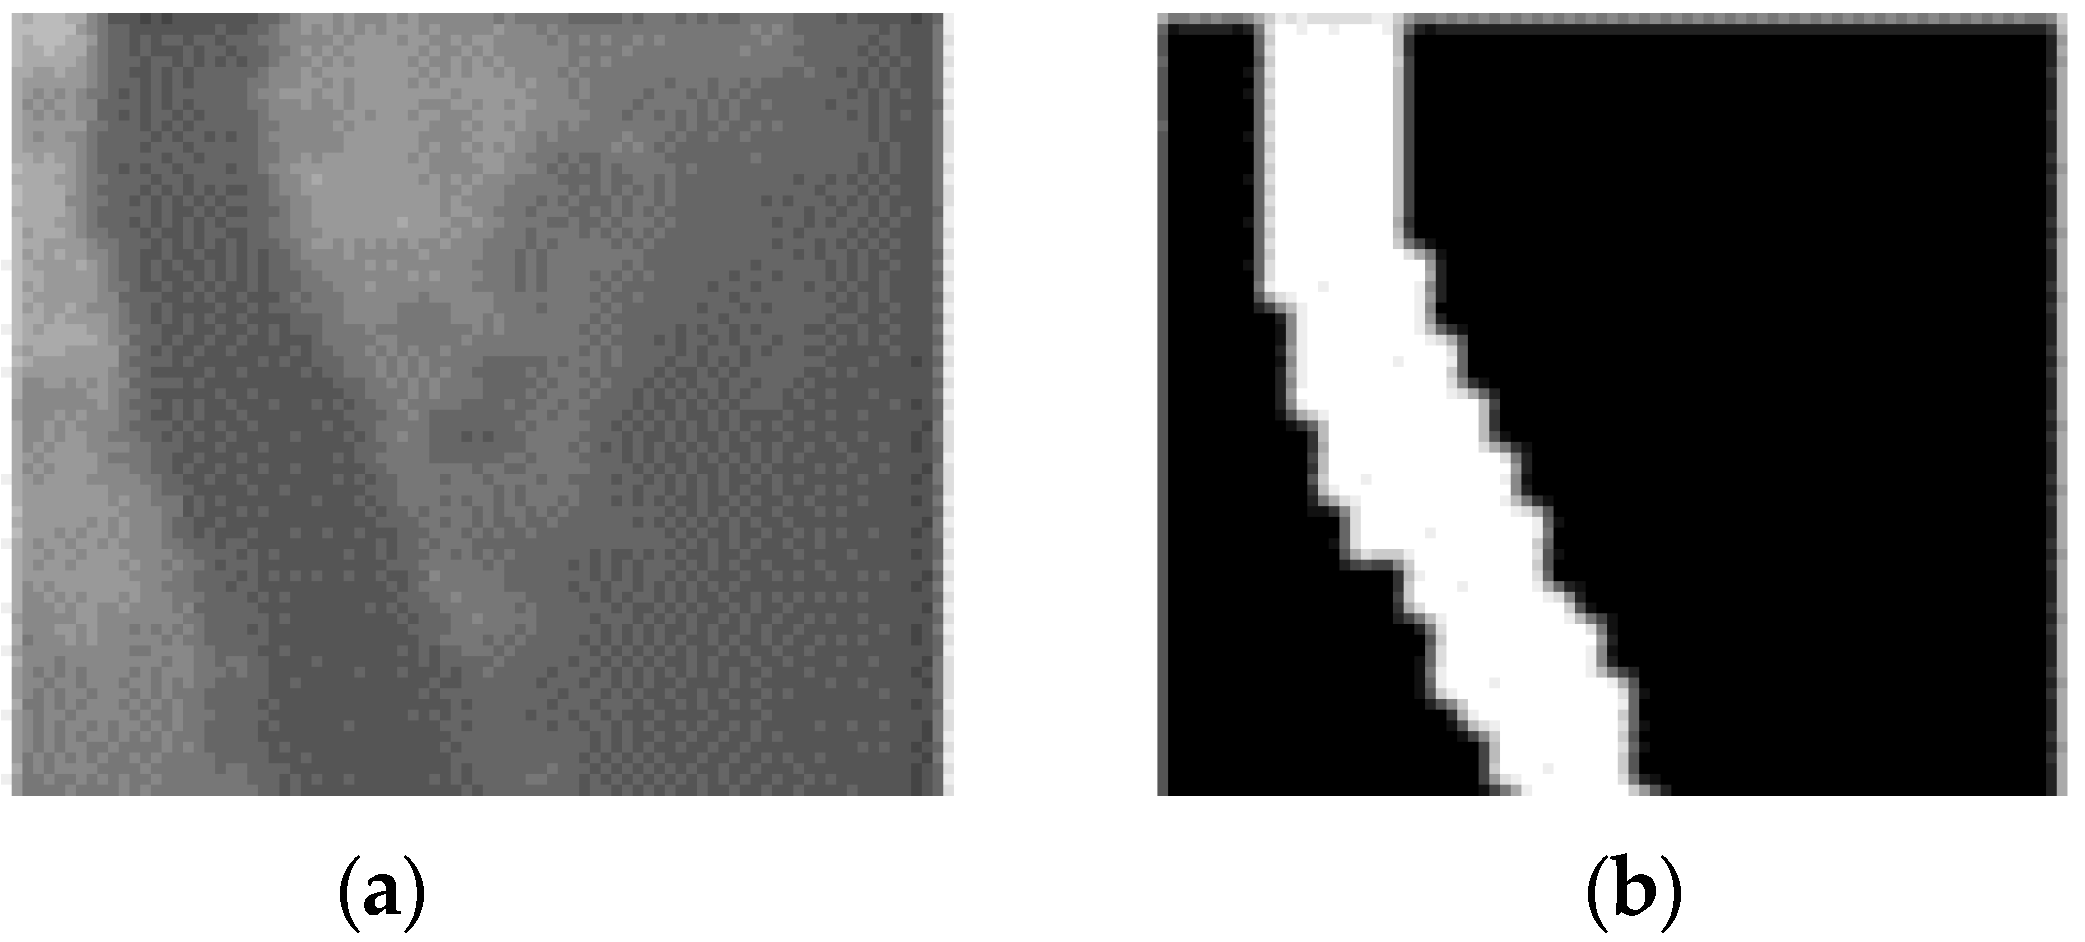

A deep and concrete comparative study has been performed to provide insight into the performance of our introduced method and compare its performance towards recent related works in the field. Comparing our autoencoder with other models (see Table 1 and Table 2), we notice that our proposed autoencoder is trained in fewer epochs and performs quite well. Also, it has the highest specificity. It should be noted that the training process of other models lasts many hours since they are trained with 100–150 epochs. Specifically, the SA-UNet proposed by Guo et al. [30] is the newest model with the best overall performance trained in 150 epochs. On the other hand, our proposed convolutional autoencoder is trained significantly faster (within 35 min), and its results are very competitive, with the specificity surpassing any other model’s. Specificity essentially measures the percentage of correct black pixels in evaluation images. This can be seen from the final result, after which the images are pretty “clean” without the noise we observe in other models. For example, an attempt at automatic segmentation of the blood vessels by the model of Fan et al. is shown in Figure 8. On the left, we can observe that the octave convolutional neural network adds enough noise in the final attempt to segment the retina image.

On the contrary, our convolutional autoencoder has a more precise result without noise. These photos belong to the STARE database. It is important to emphasise that in the DRIVE database, each image’s masks are available, allowing us to calculate the performance metrics only in the FOV (field of view) and not in the pixels of the background. In the STARE database, the masks are unavailable; therefore, the metric evaluation results include all the images’ pixels.

Figure 8. Comparison against existing method. (a) An attempt of automatic segmentation by the Octave Convolution Neural Network [45]. (b) The corresponding automated vessel segmentation of our proposed convolutional autoencoder.